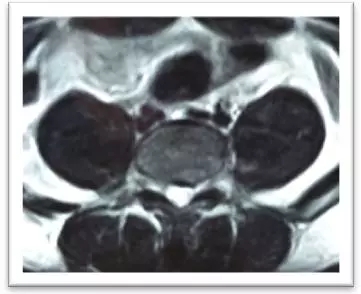

(術(shù)后)

摘除后,患者即感左下肢酸脹消失,直腿抬高試驗陰性,2天后即可下地行走,術(shù)后10天拆線出院。小姚對療效非常滿意。